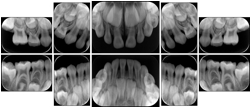

6 Standard Pedodontic A Dental Image Layout

DL-P001A